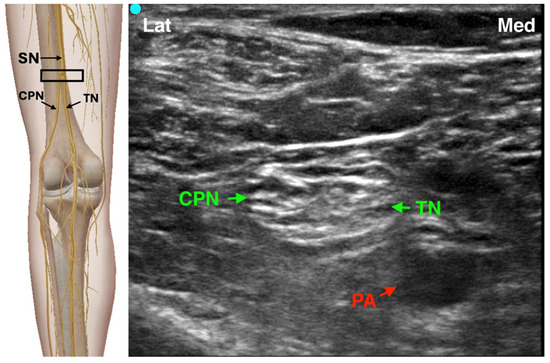

4.2. Popliteal Sciatic Nerve Block

The popliteal sciatic nerve block (PSNB) is one of the most frequently used techniques for foot and ankle surgery, including Achilles tendon repair, ankle fracture fixation, and forefoot reconstruction [7]. The block is performed in the popliteal fossa before the sciatic nerve divides into the tibial and common peroneal nerves, enabling effective anesthesia of the distal lower limb. Historically, several landmark-based techniques have been developed using peripheral nerve stimulation (PNS) to identify the nerve structures. These remain useful when ultrasound is unavailable or as an adjunct to enhance accuracy. Two main approaches were commonly used: the posterior approach, with the patient in prone decubitus position, the needle was inserted between the tendons of the hamstring muscles (semitendinosus/semimembranosus and biceps femori) 7–10 cm cranial to the popliteal crease; the lateral approach, with the patient in supine position, the needle was inserted in the groove between the vastus lateralis and biceps femoris, approximately 10 cm proximal to the lateral femoral condyle, it is advanced until contact with the femur, then withdrawn to the level of the skin and redirected approximately 30° posteriorly [10].

We highlight that lateral positioning is generally preferred to the prone position due to improved patient comfort.

During PNS-guided blocks, stimulation is typically started at 1–2 mA and reduced to 0.5 mA once a motor response is elicited. Plantarflexion and inversion suggest tibial nerve component stimulation, while dorsiflexion and eversion indicate DPN component stimulation. The introduction of ultrasound guidance has transformed PSNB practice, offering real-time visualization of the sciatic nerve and surrounding anatomy, and improving safety and block success [11,12,13]. The procedure can be performed with the patient in lateral or prone position using a high-frequency linear probe. The sciatic nerve is identified in the popliteal fossa, and the needle is advanced in- or out-of-plane to deposit 20–30 mL of local anesthetic (e.g., ropivacaine 0.5% or bupivacaine 0.25%) around the nerve [13] (Figure 2). Recent developments include the sub-sheath and extra-sheath approaches, where local anesthetic is injected within or outside the paraneural sheath, respectively. Sub-sheath injections may yield faster onset, although with a higher risk of nerve injury [14,15]. In order to avoid such events, the adjunct of opening injection pressure monitoring may be helpful to ensure a more precise and safe needle positioning, though further studies are warranted to assess long-term outcomes and optimal dosing strategies [16]. Clinical studies show that PSNB provides prolonged postoperative analgesia, reduces opioid requirements, and avoids systemic side effects typical of neuraxial anesthesia. Continuous popliteal sciatic nerve block plays a relevant role in managing more complex and painful procedures, showing comparable outcomes in terms of postoperative pain relief and patient satisfaction. However, current evidence remains limited regarding its safety profile, and further large-scale studies are required to validate its long-term efficacy and safety [17]. Compared to spinal anesthesia, it has demonstrated superior patient satisfaction and fewer complications such as hypotension or urinary retention, making it an attractive option for hallux valgus and other forefoot surgeries [18].

Figure 2. Ultrasound-guided Popliteal Sciatic nerve Block SN: Sciatic Nerve; TN: Tibial Nerve; CPN: Common Peroneal Nerve; PA: Popliteal Artery; The black rectangle indicates the placement of the ultrasound probe on the anatomical area.